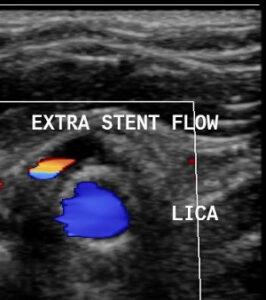

Master the intricacies of evaluating carotid stents with duplex ultrasound in this specialized course. Learn standardized ultrasound protocols for optimal imaging, including spectral Doppler techniques and color flow imaging, tailored to detect stent-related complications. Explore diagnostic criteria for restenosis, neointimal hyperplasia, and vessel wall injuries. Gain insights into velocity thresholds, post-stenotic turbulence, and follow-up intervals for long-term stent surveillance. Ideal for sonographers and physicians, this course equips you to enhance diagnostic accuracy and ensure effective management of patients with carotid artery stents.

Identify commonly encountered pathology associated with carotid stents